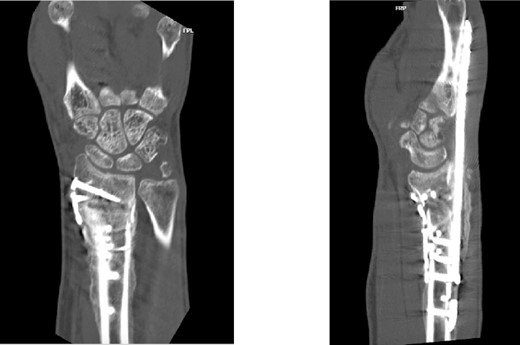

Two weeks following the procedure, the patient returned to the clinic for a follow-up visit. The wrist was swollen and ROM was limited. Hand motor functions and neurovascular exam were fully intact. Radiographs taken in clinic showed intact hardware with healing fracture. At 2 months follow-up, radiographs showed intact hardware with interval bone bridging across fracture sites. Radiographic parameters including articular alignment, radial height, radial inclination, and volar tilt were in acceptable ranges (Fig. 5). The patient reported no concerns or complications. A computed tomography (CT) scan was obtained at 10 weeks after the procedure and confirmed adequate bony healing and alignment without failure (Fig. 6). The dorsal spanning plate was eventually removed 1 month later and 4 months since the initial operation (Fig. 7).

CT assessment at 10 weeks postprocedure with coronal and sagittal cuts.

Furthermore, even though retrieval of the dorsal spanning plate did not occur until 4 months after the procedure, our patient’s CT demonstrated adequate fracture consolidation, alignment, and readiness for hardware removal by the 10-week mark. Traditionally, dorsal spanning plates are left in place for at least 12 weeks to ensure adequate fracture consolidation [6, 7]. It is likely that additional augmentation of the dorsal spanning plate with selective open reduction internal fixation in our case may have decreased time to acceptable fracture healing for plate removal. As a result, this would theoretically result in earlier ROM and return to normal activities, potentially improving clinical outcomes. However, our case was limited in its ability to adequately assess final ROM and functional abilities due to loss to follow-up.